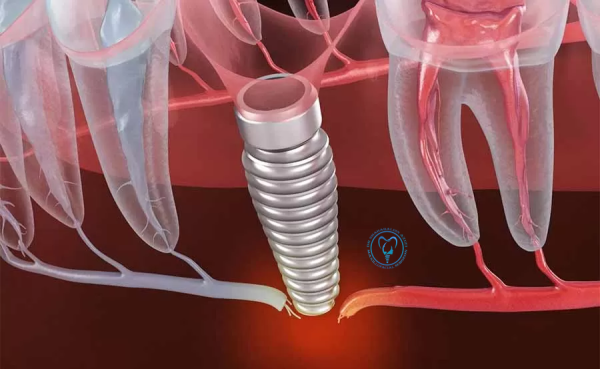

بی حسی لب و چانه بعد از ایمپلنت

4-بیحسی لب و چانه بعد از ایمپلنت دندان — علت، درمان و پیشگیری فهرست مطالب این مشکل چیست؟ علائم شایع چرا بعد از ایمپلنت بیحسی رخ میدهد؟ چه زمانی باید نگران شد؟ تشخیص (چه کارهایی انجام میشود) چه کارهایی میتوان کرد — از ساده تا جراحی زمان بهبود و انتظارها روشهای پیشگیری پرسشهای پرتکرار این…